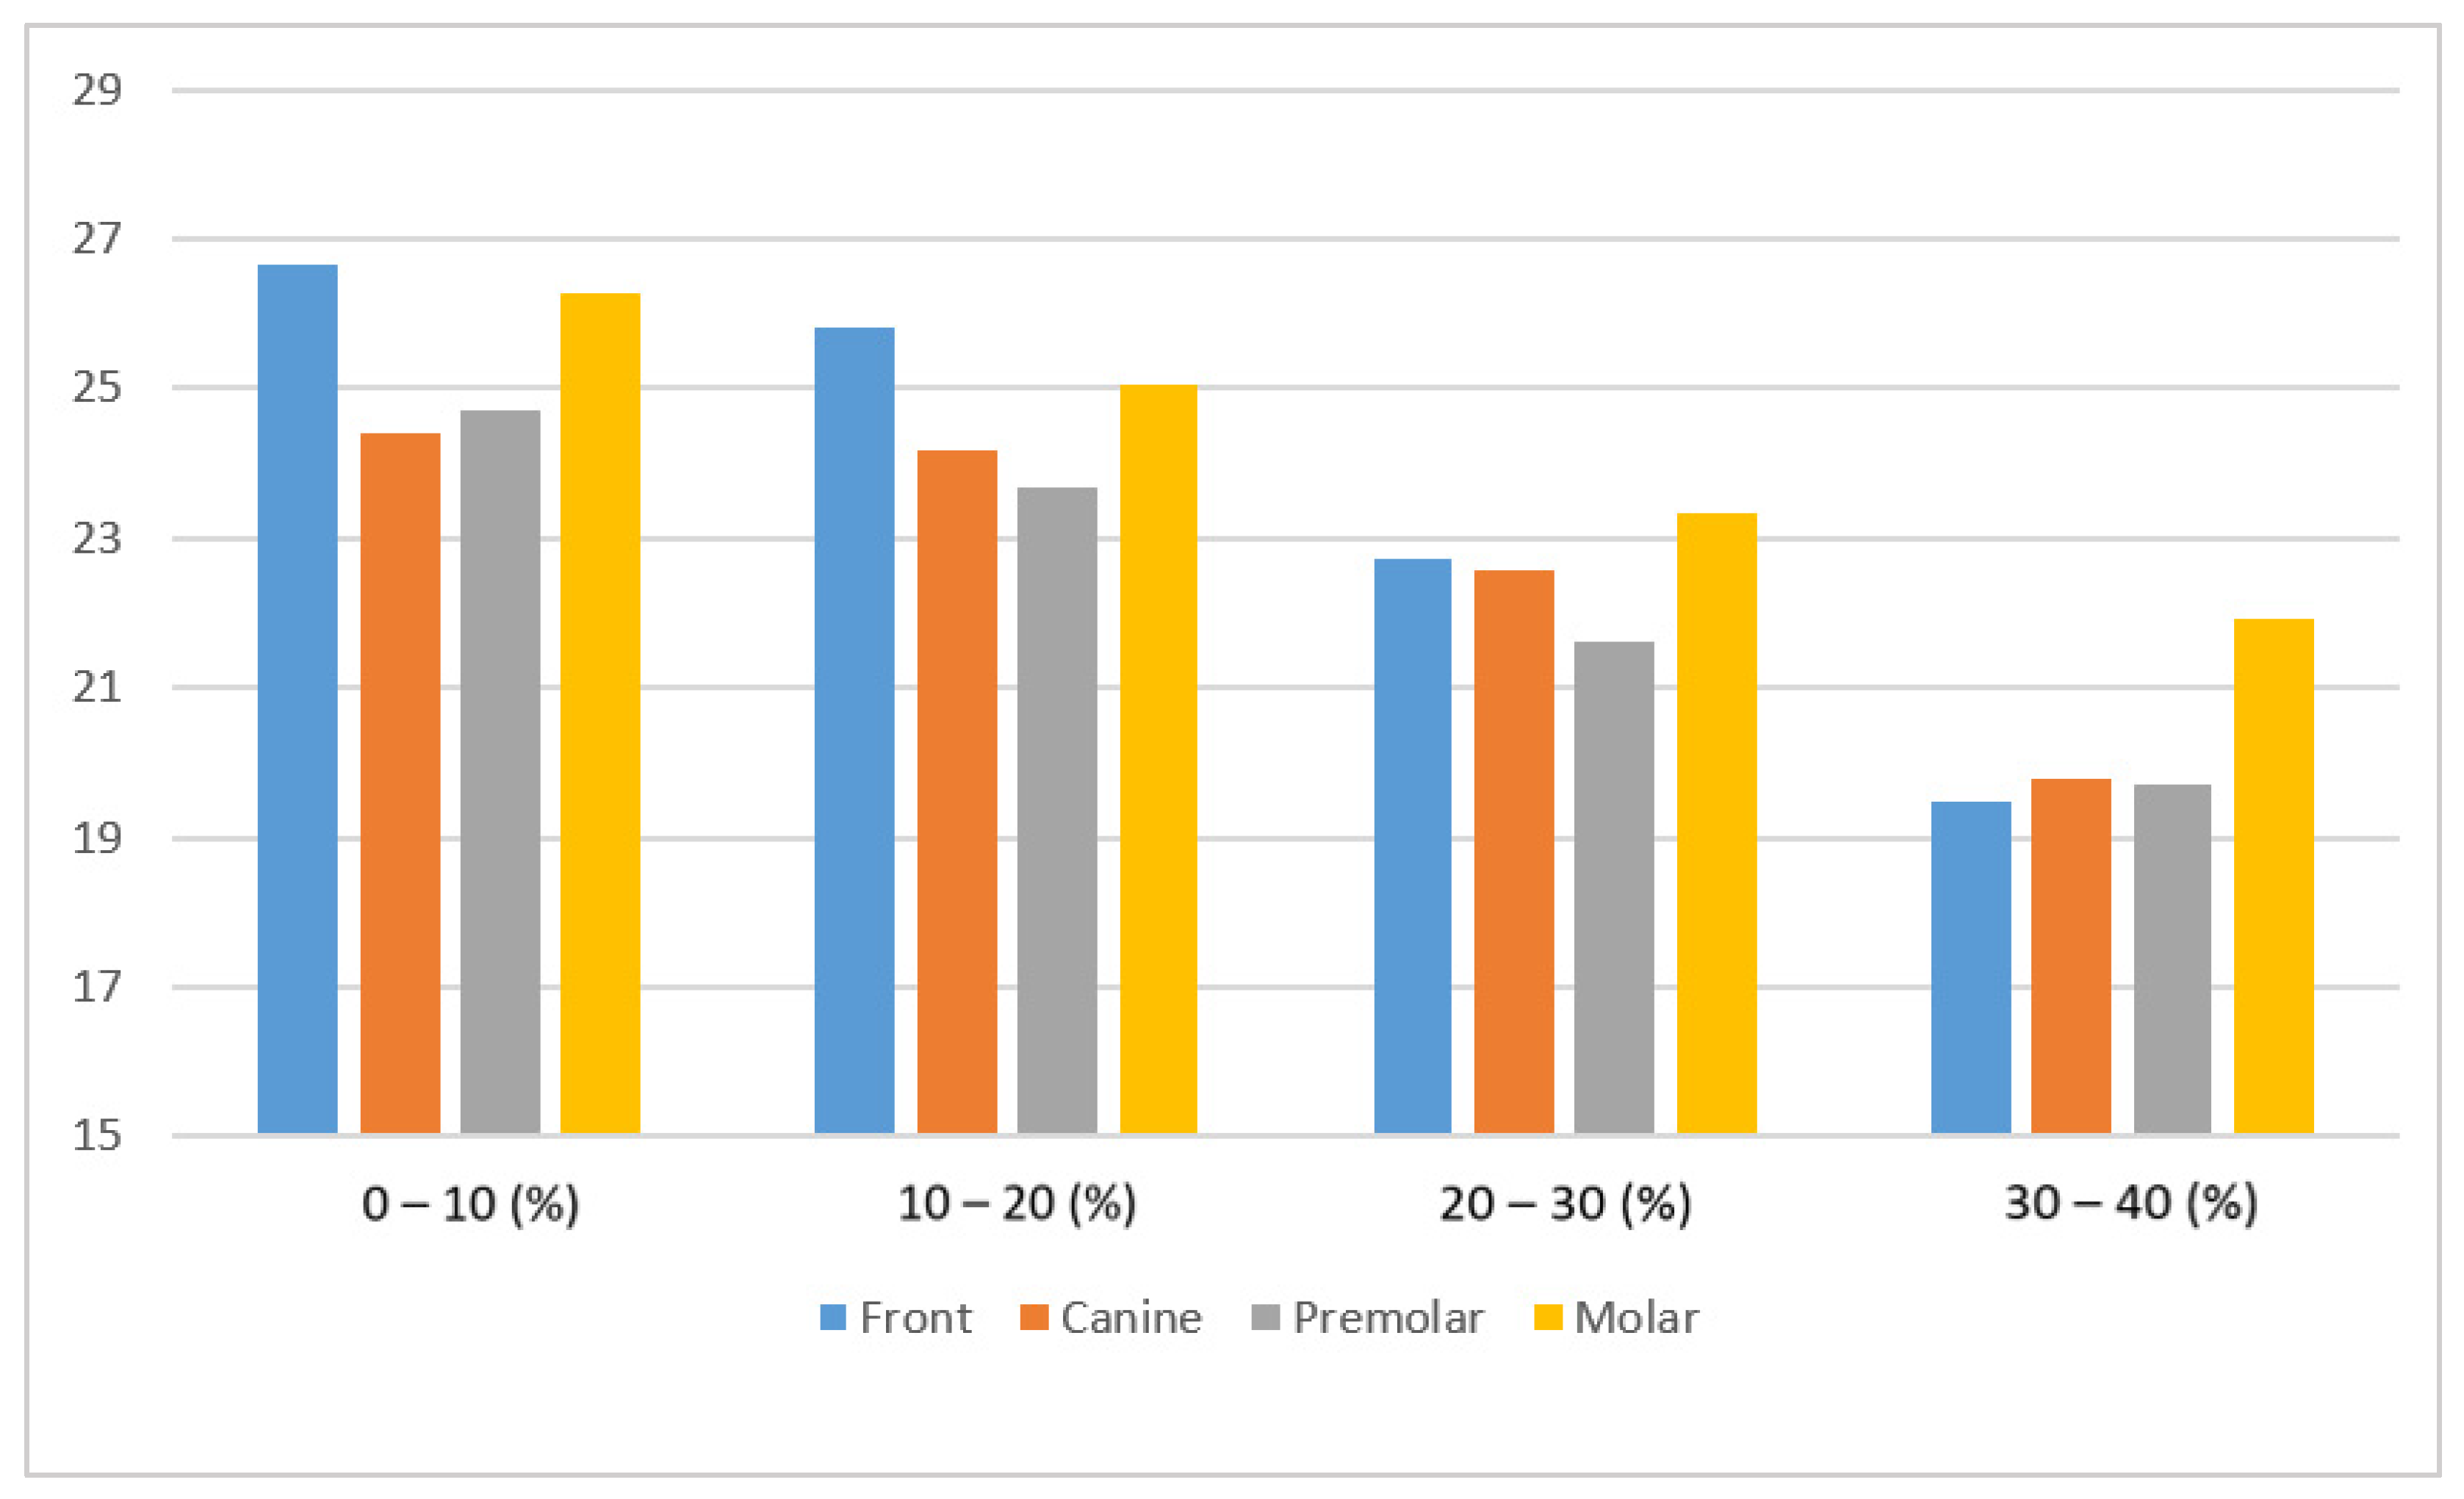

3.2.3. Measurement Accuracy Results

| Mask | Incisor | Canine | Premolar | Molar |

|---|---|---|---|---|

| 0–10% | 26.68 | 24.42 | 24.71 | 26.27 |

| 10–20% | 25.82 | 24.19 | 23.69 | 25.07 |

| 20–30% | 22.72 | 22.57 | 21.62 | 23.33 |

| 30–40% | 19.49 | 19.78 | 19.71 | 21.93 |